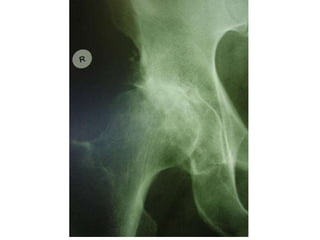

X-RAY OF HIP OA

• X-ray shows

osteophytes,

subchondral

sclerosis, and

complete loss of joint

space

• Patients often

present with deep

groin pain that

radiates into the

medial thigh

Hip Joint

• X-ray shows osteophytes, subchondral sclerosis,and complete loss of joint space • Patients often present with deep groin pain that radiates into the medial thigh Hip Joint